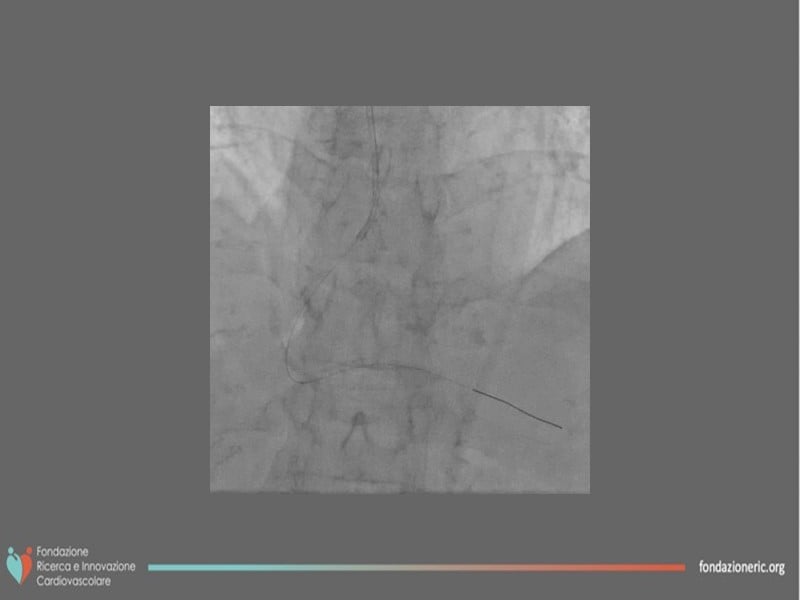

Thanks to the different interventions of this EuroPCR 2022 session, understand the role of paclitaxel DCB in modern era interventional cardiology, the differences, and advantages versus DES, the role of blended therapies in CLS, and learn how to correctly prepare the lesion and obtain the best from this technology on the long term.